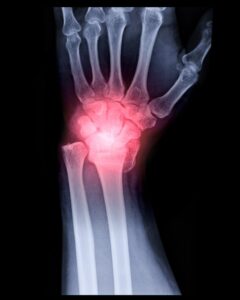

Distal Radius Fracture Compensation Claims In The UK

By Cat Reeves. Last Updated 12th June 2025. Welcome to our guide about a distal radius fracture compensation claim. If you suffered an injury in an accident caused by someone else’s negligence, you may be eligible to make a personal injury claim.